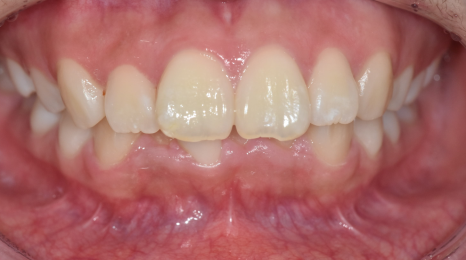

교합 상태, 치아 배열 상태를 확인하기 위해

5분할 포토라 불리는 구강 내 사진을 찍고

뽄도 뜹니다.

교정 모델을 만들기도 하며

이 과정에서 구강 스캐너가 동원되기도 합니다.

앞으로 교정을 통해 치아가 어떻게 움직일지 예측합니다.